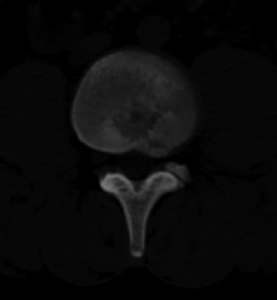

男,20,士兵,腰痛3年多,无外伤史

都是同一幅图啊,椎体内椎间盘突出。

考虑:1、多发许莫尔氏结节形成;

2、建议平行腰5椎体扫描或冠矢状曲面重建除外椎弓峡部断裂。

1、多发许莫尔氏结节形成;

2、椎弓峡部断裂。

3、l5轻度滑脱。

1、多发许莫氏结节。

2、腰5双侧椎弓峡部崩裂并i度前滑脱,楼主椎间盘扫描角度有问题,另外需要反倾角扫描腰5椎弓峡部。

2、腰5双侧椎弓峡部崩裂并i度前滑脱。